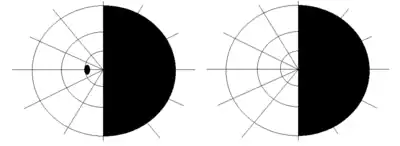

In the retina, the syndrome causes retinocephalic vascular malformations that tend to be present with intracranial hemorrhage and lead to decreased visual acuity, proptosis, pupillary defects, optic atrophy, congestion of bulbar conjunctiva, and visual field defects.[4][5] Retinal lesions can be unilateral and tortuous, and symptoms begin to appear in the second and third decades of life.[4]

Typically not diagnosed until late childhood or later, Bonnet–Dechaume–Blanc syndrome usually presents itself with a combination of central nervous system features (midbrain), ophthalmic features (retina), and facial features.[7] The degree of expression of the syndrome's components varies both clinically and structurally. Common symptoms that lead to diagnosis are headaches, retro-orbital pain, and hemianopia.[5]

The ophthalmic features of Bonnet–Dechaume–Blanc syndrome occur as retinal arteriovenous malformation (AVMs). There are three categories of AVMs based on their severity. The first category consists of the patient having small lesions that usually are asymptomatic. The second category, more severe than the first, is when the patient's malformation is missing a connecting capillary between an artery and a vein; without it, edema, hemorrhage, and visual impairment can result. Category three refers to malformations so severe that their dilated vessels no longer distinguish between artery and vein, and the patient has a significantly increased risk of vision loss.[3] Since the retinal lesions categorized vary from large vascular malformations that affect a majority of the retina to malformations that are barely visible, the lesions can cause a wide range of symptoms, including decrease in visual sharpness, proptosis, pupillary defects, optic nerve degeneration, and visual field defects.[5] The most common type of visual field impairment due to AVMs is homonymous hemianopia,[2] which is usually unilateral.[7]